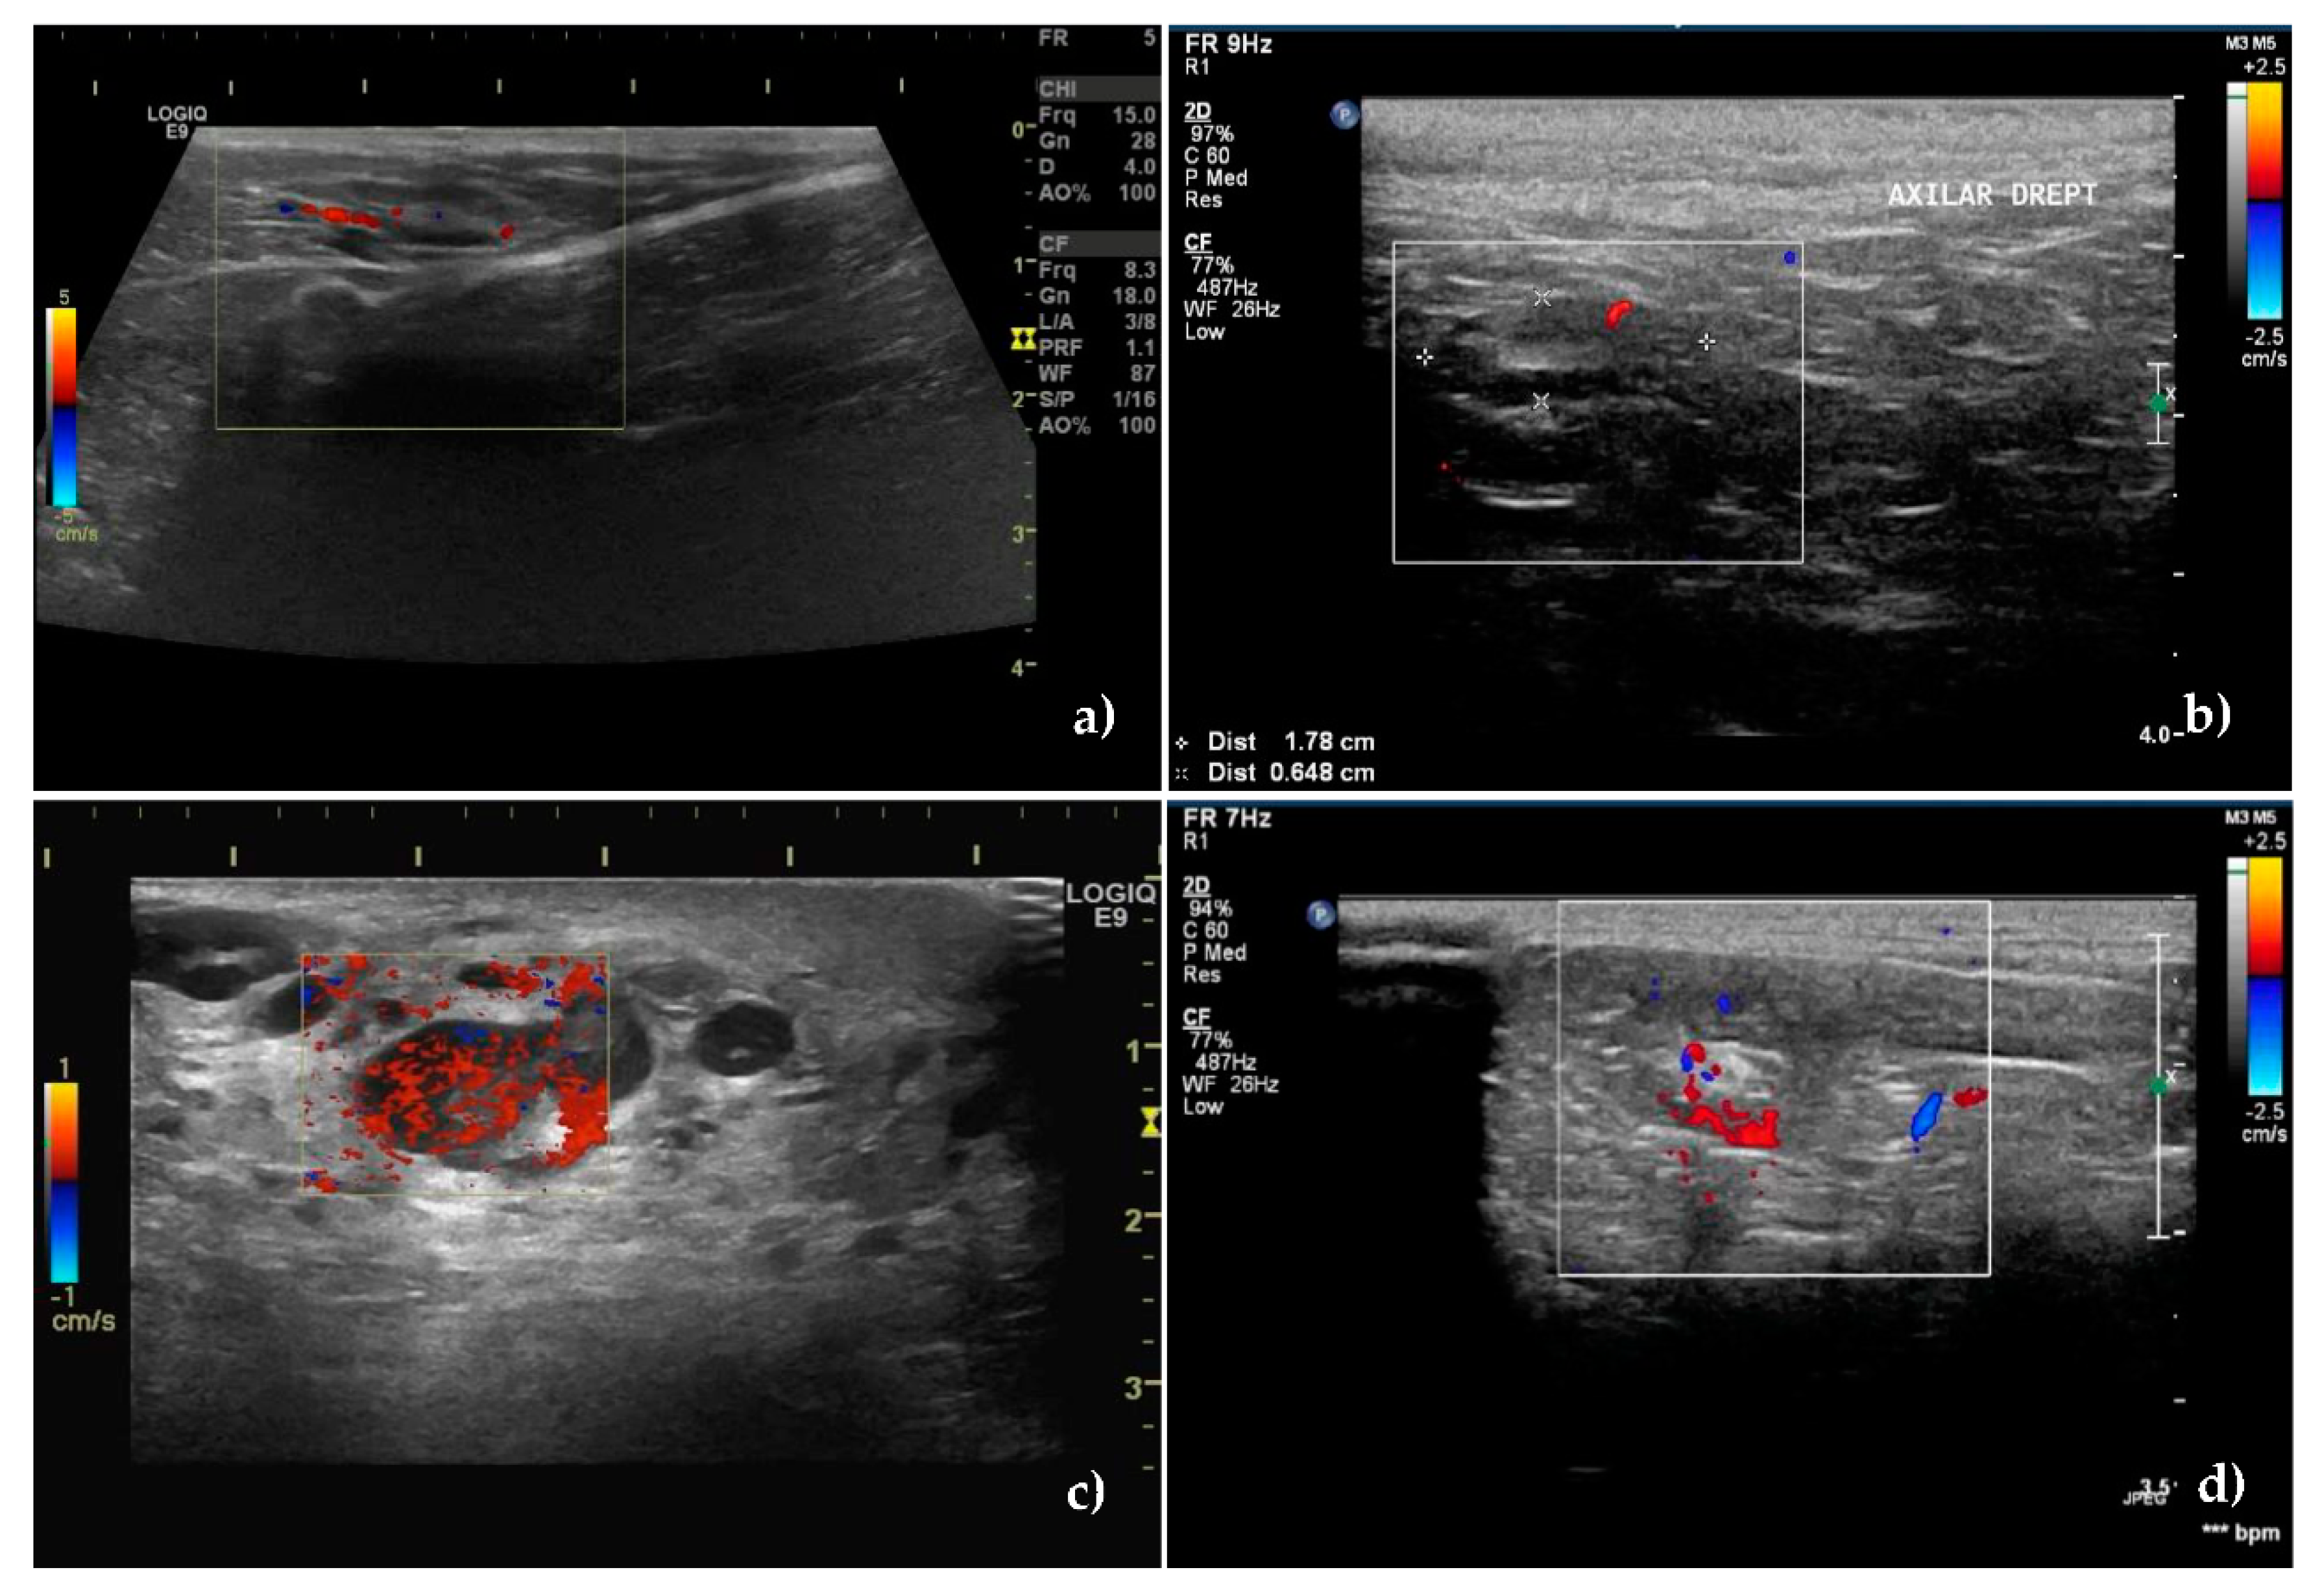

3.2. Color Doppler Ultrasonography

The Doppler technique certified the presence of a vascular signal in 40 unaffected SLNs and 53 metastatic SLNs, with different pattern between the groups, p < 0.001.

In 85.71% of non-metastatic SLNs, blood vessels started from the hilum and were orderly distributed toward the capsule (Figure 2a,b), whereas in 88.88% of the metastatic SLNs, the vascularization had a disordered, chaotic appearance, with predominantly peripherally location (55.55%) or mixed (20.37%) (Figure 2c,d). 12 metastatic SLNs had a perfused hilar region.

Figure 2. Vessels location and distribution assessed by Color Doppler ultrasound. (a) Central, hilar vessels of unaffected superficial inguinal sentinel lymph node and (b) unaffected axillary sentinel lymph node. (c) Presence of neovascularisation with an abnormal, hilar, and peripheral distribution of vessels in a metastatic superficial inguinal sentinel lymph node. (d) Mixed hilar and peripheral pattern with the parenchymal subcapsular location of vessels in a metastatic axillary sentinel lymph node.

Regarding the intranodal vascular resistance, the mean values of the resistivity index (RI), were lower in the unaffected nodes: 0.50 ± 0.14 vs. 0.70 ± 0.13 in the metastatic SLNs (p < 0.001).

The same trend was also recorded for the pulsatility index (PI). Its mean value was lower in the unaffected nodes 0.98 ± 0.22 compared to 1.24 ± 0.25 in the metastatic ones.

According to the ROC analysis, the cutoff value obtained for lymph node differentiation, for RI was 0.56 and for PI was 1.02 with 83% SE and 75% SP for RI and 83% SE respectively a 65% SP for PI (Figure 3b).

The accuracy of the two methods was 80% for RI and 75.14% for PI.